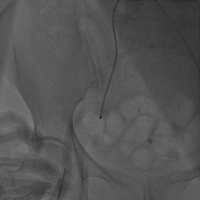

然后进行主动脉根部造影,导丝跨瓣,并进行术前测压评估(Figure 9)。选用大小合适的球囊,进行球囊扩张,评估瓣环上结构,指导选择瓣膜尺寸,这对钙化严重的二叶瓣畸形的患者尤其重要。(Figure 10)

Figure 9

术前测压

Figure 10

3. 主动脉根部造影

4. 导丝跨瓣

5. 测压